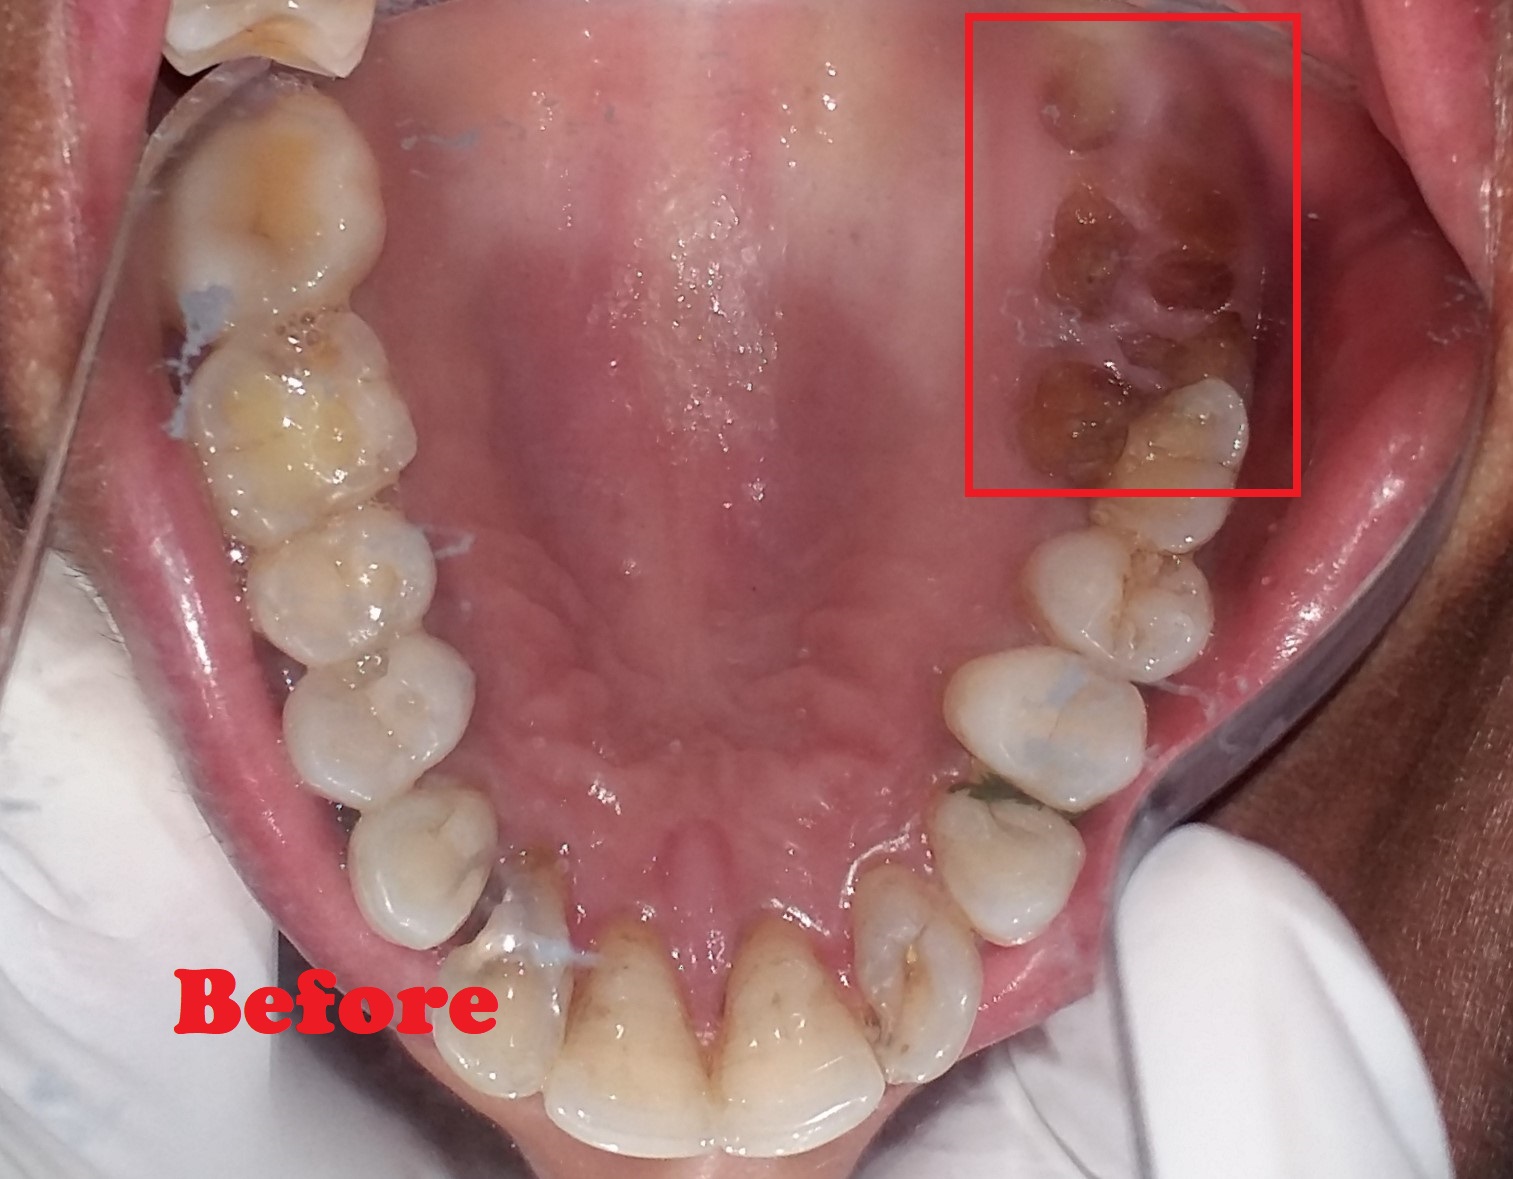

- Removes infected nerve tissue while preserving your natural tooth.

- Relieves pain, swelling, and sensitivity caused by deep decay or infection.

- Protects against tooth extraction and maintains natural biting ability.